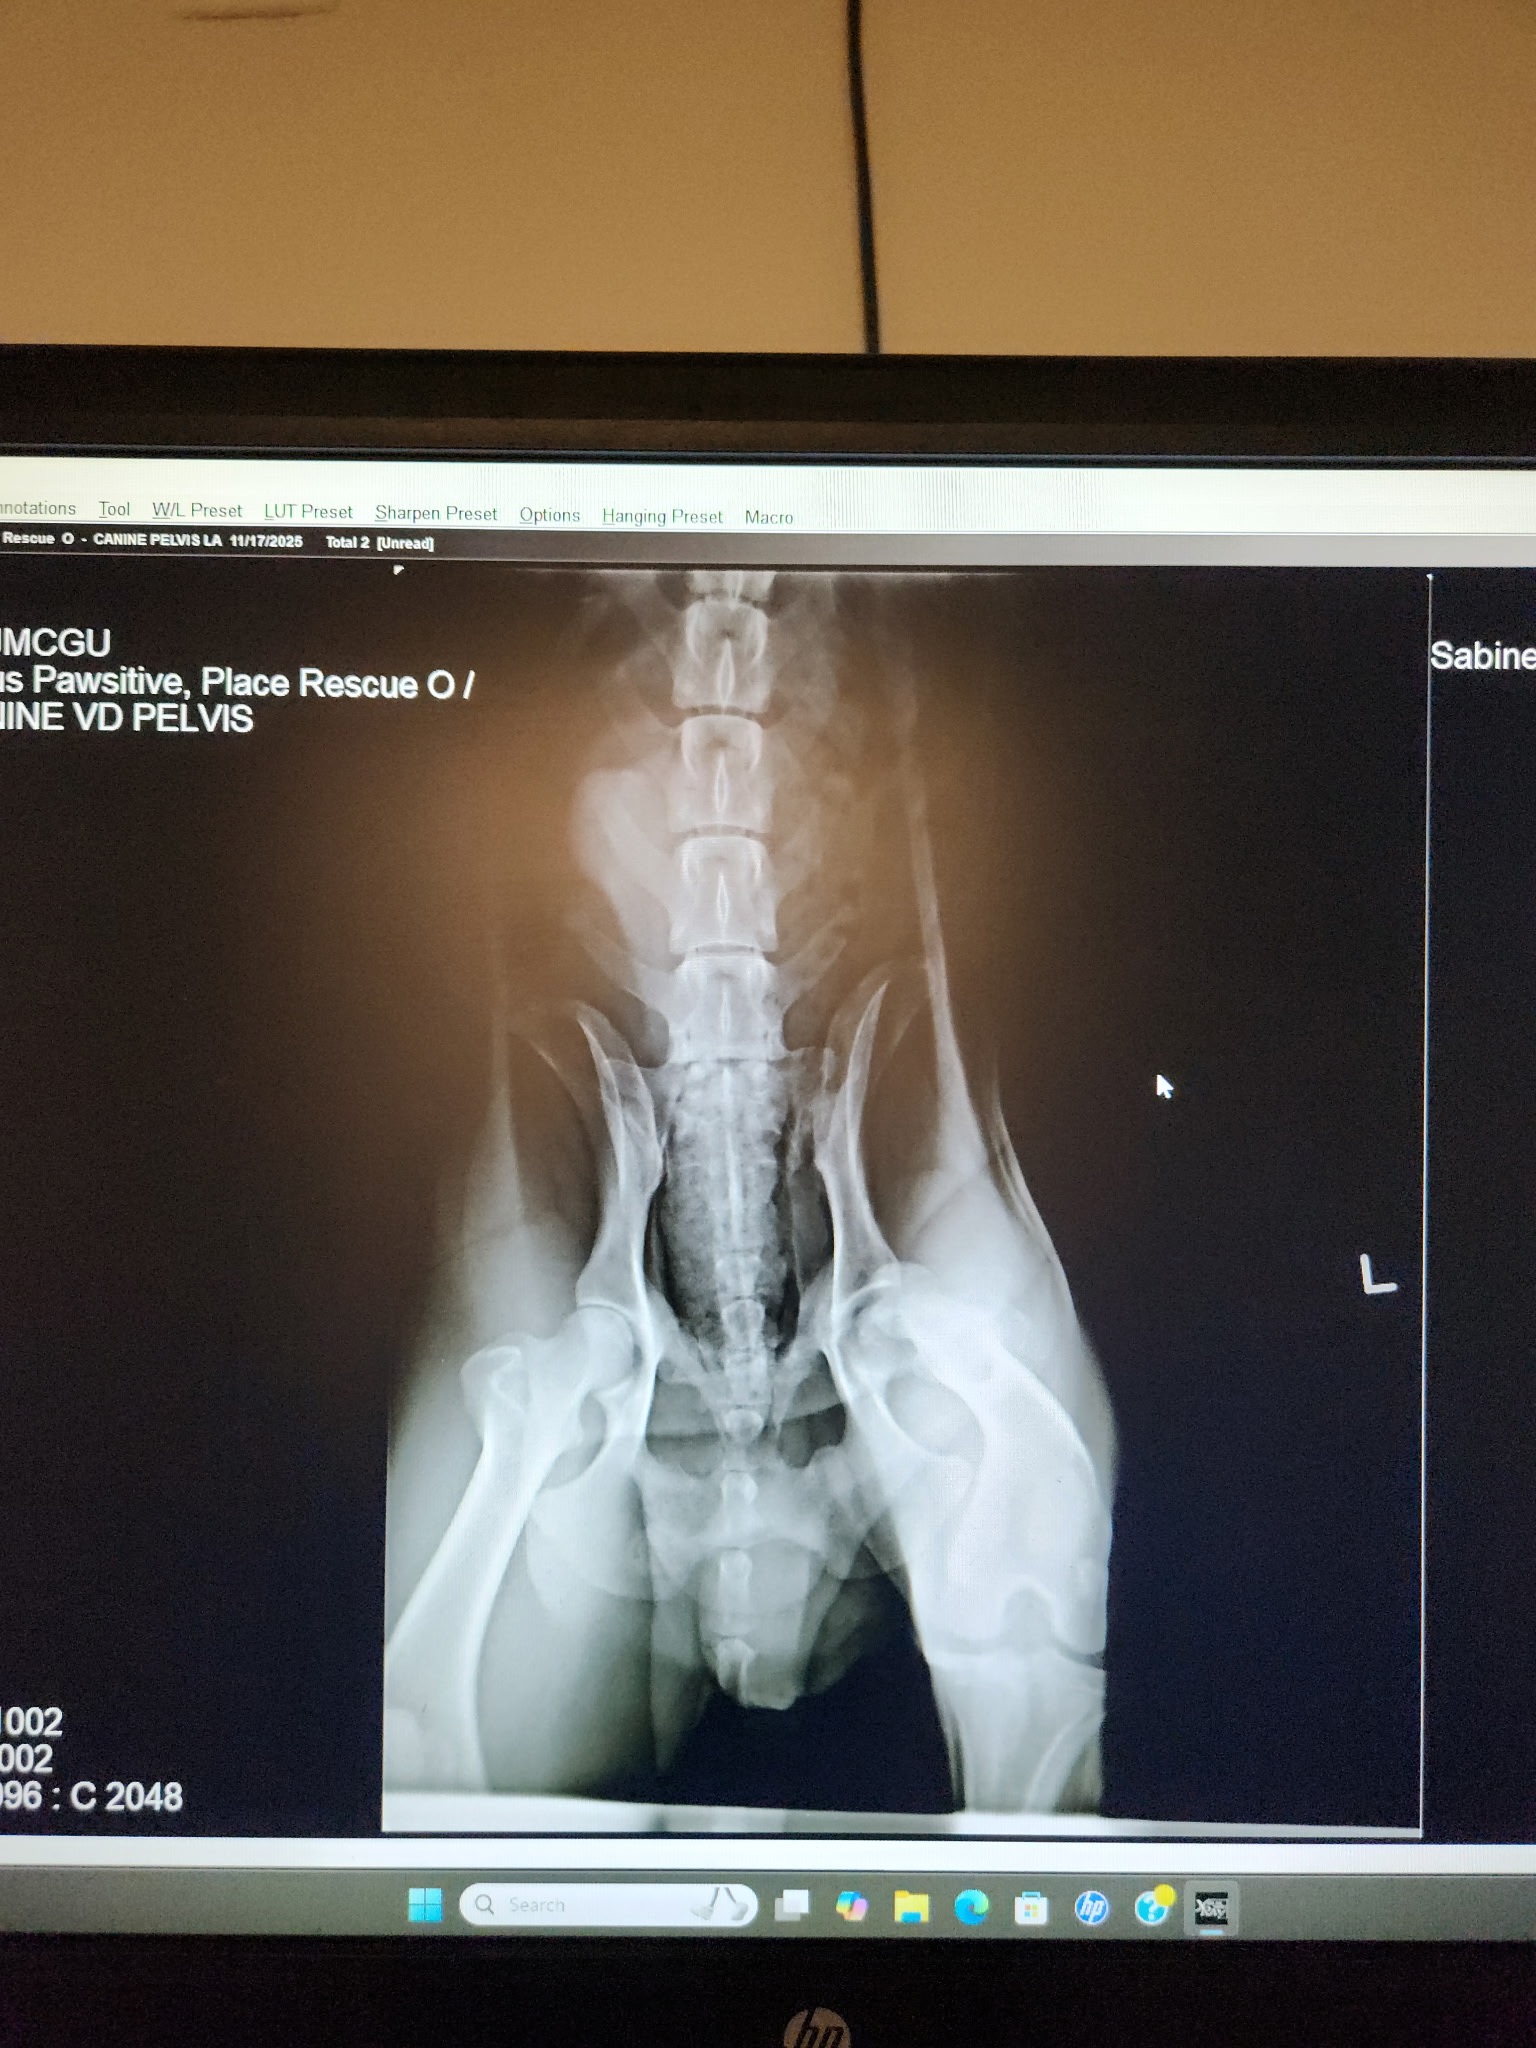

Recently we shared about the sweet chocolate lab found limping along 69 in Bullard TX, and today we finally have answers. Rufus’s left leg is completely separated from his hip joint, and he will need orthopedic surgery to have it screwed back into place. The estimated cost for his surgery is $1,600‼️